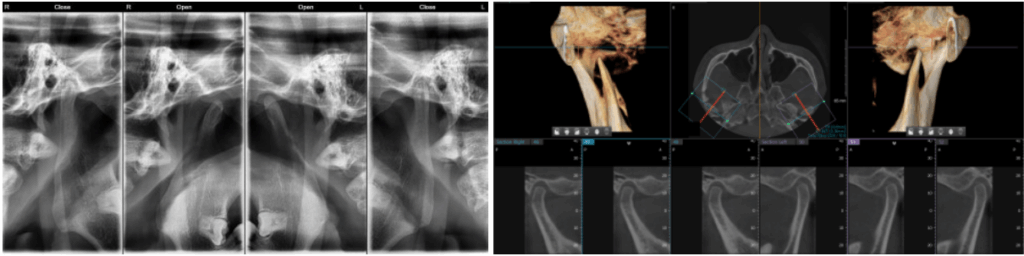

추가로 턱관절 검사를 시행했습니다.

턱관절은 측두골과 하악골을 역할을 하며,

음식을 먹거나 말을 할 때

움직이면서 사용하게 되는데요.

자연치의 교합 상태와 밀접한 관련이 있어

배열이 틀어질 경우 턱관절 관계에

문제가 생길 수 있습니다.

따라서, 이것은 이가 이동하였을 때

어금니끼리 맞물리는 위치가 변하게 되면

턱에도 영향줄 수 있기에

턱관절 검사를 같이 하는 것이 좋습니다.

23.11.24

치근의 길이는 양호한 것까지

확인한 뒤 다음과 같은

계획을 수립할 수 있습니다.